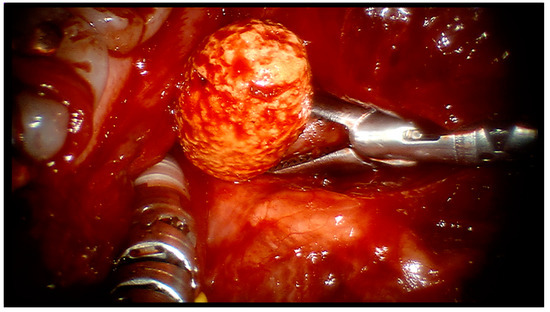

The calculus was then pushed up and away from the gland’s hilo-parenchymal region, and the surgical cavity was carefully and thoroughly irrigated with saline solution to clear out any debris (Figure 3).

Figure 3.

Removing the right salivary stone with da Vinci’s robotic arms.